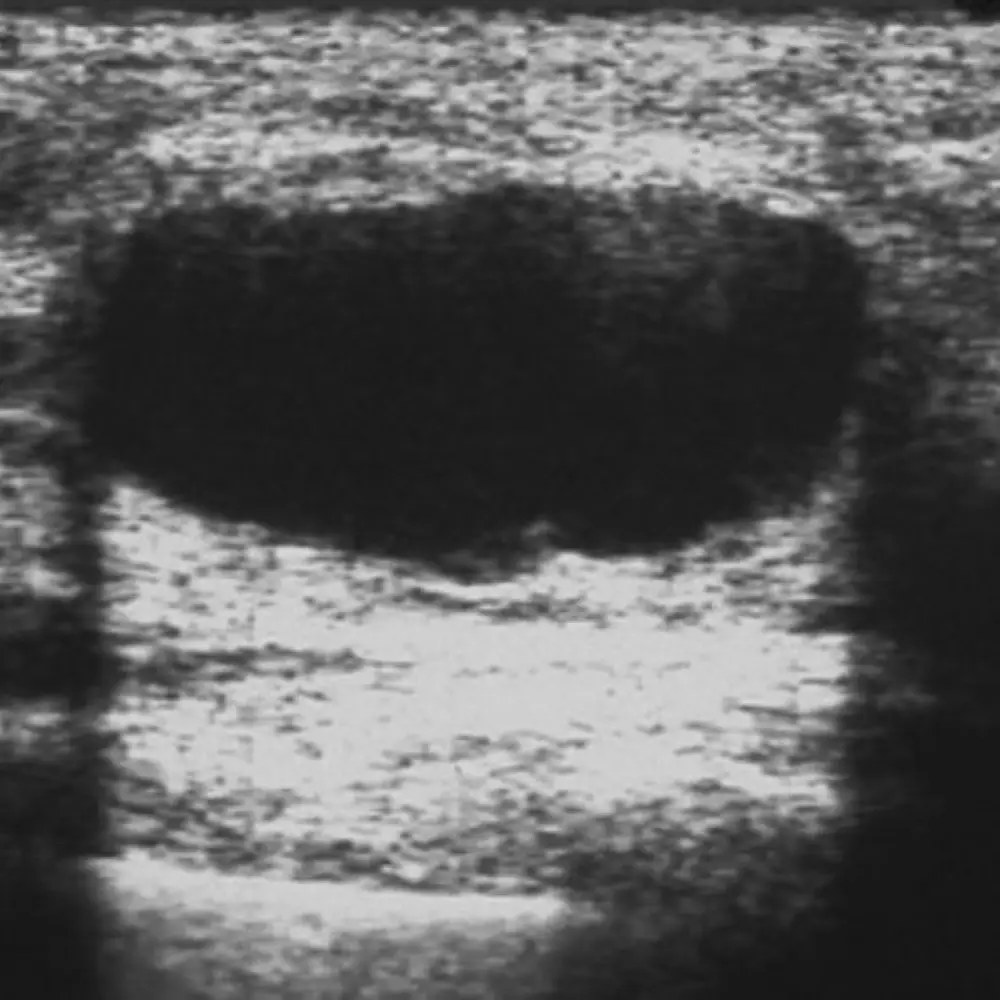

Breast cysts